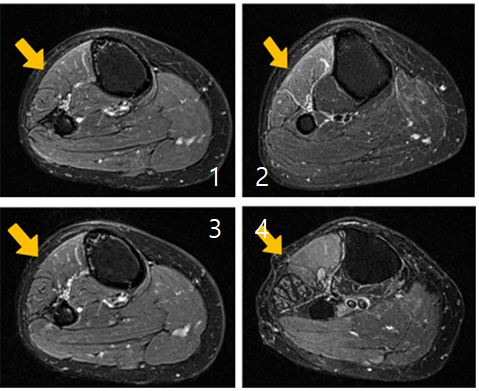

비골신경병증은 무릎 바깥쪽을 지나는 신경이 근육이나 섬유성 조직 등에 의해 압박되면서 발생하는 질환이다.

대표 증상은 발목을 들어 올리지 못하는 족하수로 걸을 때 발끝이 바닥에 걸리거나 계단 이용 시 불안정한 보행이 나타난다.